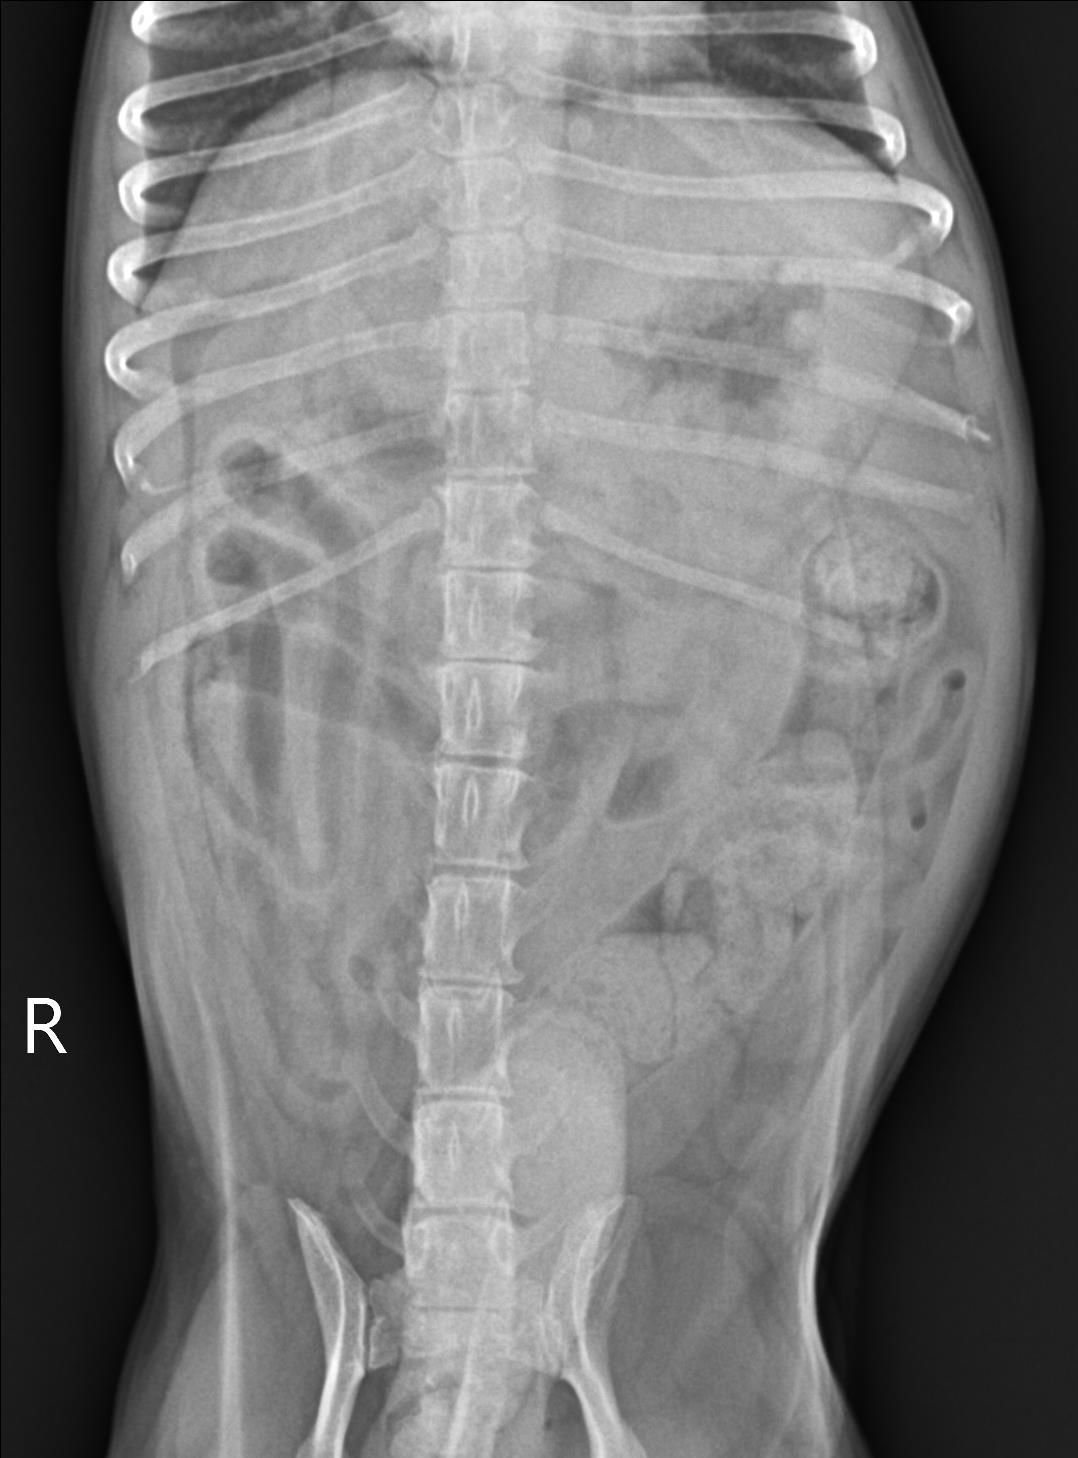

- 흉복부 방사선 검사

X-ray 상으로는 심장과 폐야, 복강에서 특이적 문제를 확인하지 못했습니다.